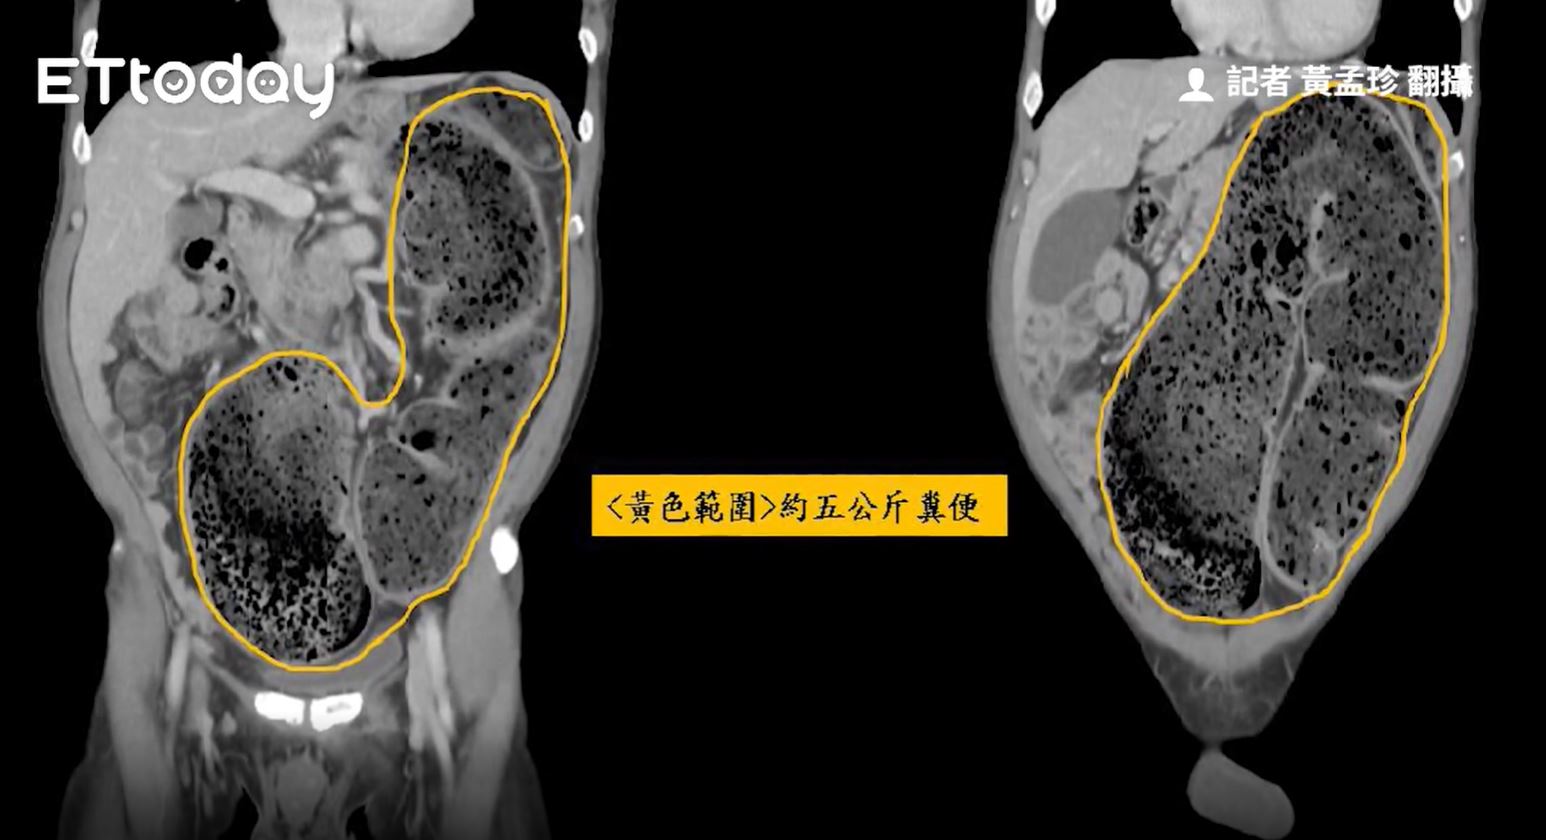

• ชายจีนไม่ขับถ่าย 20 วัน ทำอุจจาระเต็มท้อง 5 กก.